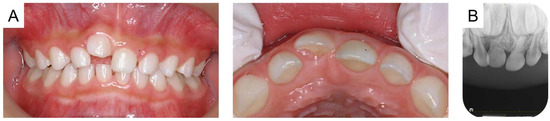

The maxillary right primary central incisor was diagnosed as an ankylosed tooth caused by trauma, and the authors continued to monitor the tooth because there were no subjective symptoms or signs of inflammation. Time-lapse photographs of the oral cavity are shown in Figure 2, Figure 3 and Figure 4. The maxillary right primary incisor continued to move labially and rootward over time; however, there were no other notable events during the next 2 years.

Figure 2. Images at the age of 5 years and 2 months: (A) intraoral photographs and (B) periapical radiograph.